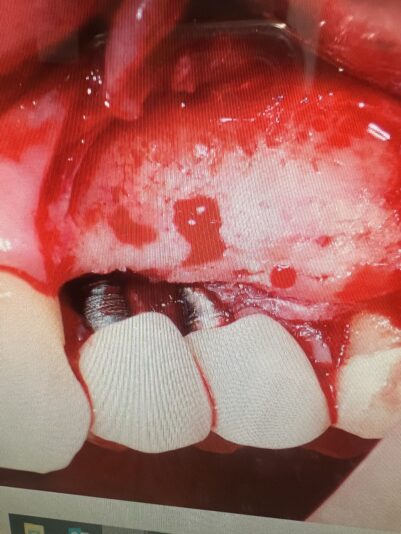

• As discussed in one of the previous posts on mini implants. For me they can be a pain to get out. I had this patient with bleeding and suppuration around these implants. I discussed with patient long term prognosis and she wanted to keep as ling as possible. So I did aome graftint and it actually turned out pretty good! Tissues are nice…